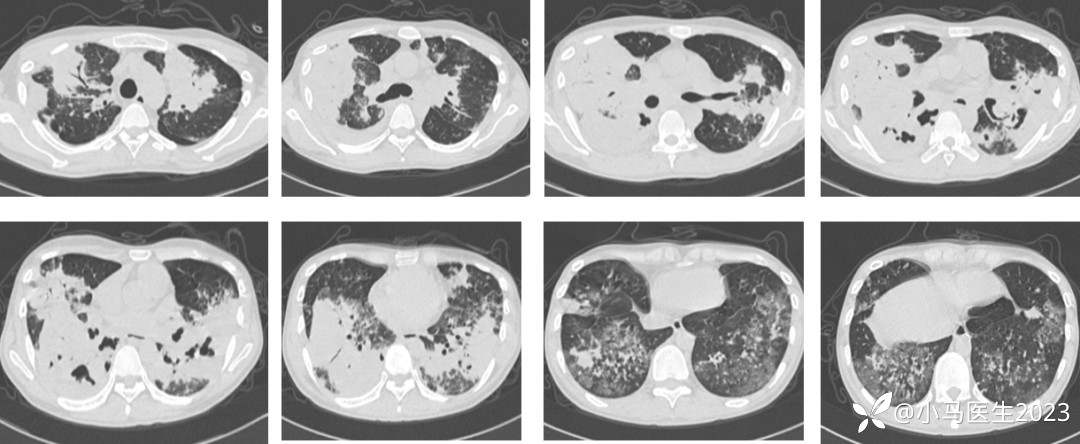

患者要求经验性治疗,予甲泼尼龙40mg qd×7天,03-15复查

胸部CT无明显变化,予口服甲泼尼龙40mg带药出院

第四次入院 03-29

出院后第3天淋雨后咳嗽症状加重

咳黄脓痰,量约40ml/日

咯血,痰中带鲜血或血痰,量约15ml/日

胸痛加重,活动后气喘加重

颜面浮肿,颜面及躯干部散在红色斑丘疹

收入院停激素后发热

氧合指数154,经鼻高流量氧疗

03-29复查胸部CT进展

胸部CT对比